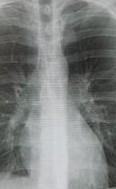

Флюорогра́фия (синонимы: радиофотография, рентгенофотография, рентгенофлюорография) — рентгенологическое исследование, заключающееся в фотографировании видимого изображения на флюоресцентном экране, которое образуется в результате прохождения рентгеновских лучей через тело (человека) и неравномерного поглощения органами и тканями организма.

Это получается мне грудь фоткать будут?

Флюрографія це майже таке саме як ренген.

Легені можуть сфоткати